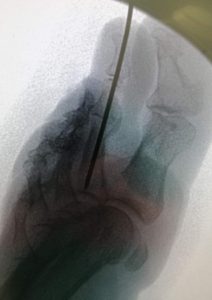

Diagnóstico por imagen de deformidades, fracturas, procesos degenerativos que afectan a los huesos.